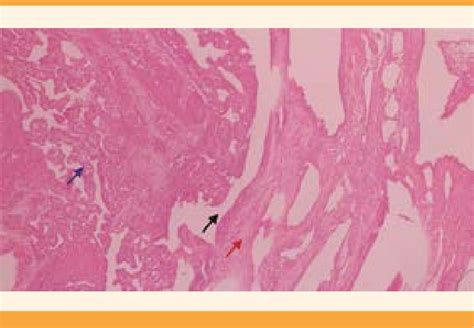

Tras comprobar el bienestar fetal, se inició tratamiento conservador para la RPM, incluyendo antibióticos (ampicilina, eritromicina, amoxicilina) y maduración pulmonar con dexametasona. El embarazo se interrumpió por vía abdominal a las 31 semanas de gestación debido al inicio de actividad uterina regular. Se realizó una cesárea, y la pieza placentaria se envió a patología. La madre fue dada de alta dos días después sin complicaciones. El reporte de patología confirmó el acretismo placentario.

El recién nacido ingresó en la unidad de cuidados intensivos neonatales por complicaciones de la prematurez, siendo dado de alta 17 días después. Este caso ilustra la complejidad de la coexistencia de placenta previa con acretismo y ruptura prematura de membranas pretérmino, una complicación poco común que requiere vigilancia materno-fetal exhaustiva y, a menudo, un manejo conservador inicial.

En la discusión del caso, se resalta la falta de publicaciones sobre la atención médica conjunta de estas dos alteraciones. Se subraya la importancia del tratamiento conservador de la RPM con esteroides, antibióticos y vigilancia estrecha, y la decisión de finalizar el embarazo en respuesta a la actividad uterina regular. La finalización del embarazo en este caso permitió prolongarlo cinco días, beneficiando al binomio madre-hijo.